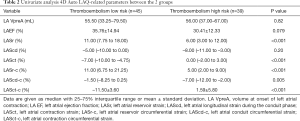

Univariate analysis of 4D Auto LAQ

Univariate analysis revealed that LASr [6.00% (3.00–12.00%) vs. 11.00% (7.75–18.00%); P<0.001], LASr-c [5.00% (2.00–9.00%) vs. 11.00% (6.75–21.25%); P<0.001], and LAScd-c [−7.00% (–12.00 to –2.00%) vs. –1.50% (–8.25–0.25%); P=0.005] were lower in the high-risk group than in the low-risk group. However, LASct [0.00% (–2.00–3.00%) vs. –7.00% (–10.00 to –4.75%); P<0.001] and LASct-c (1.59±5.80% vs. –11.50±3.60%; P<0.001) were higher in the high-risk group than in the low-risk group (P<0.001). LA VpreA, LA EF, and LAScd did not differ significantly between the 2 groups (Table 2).